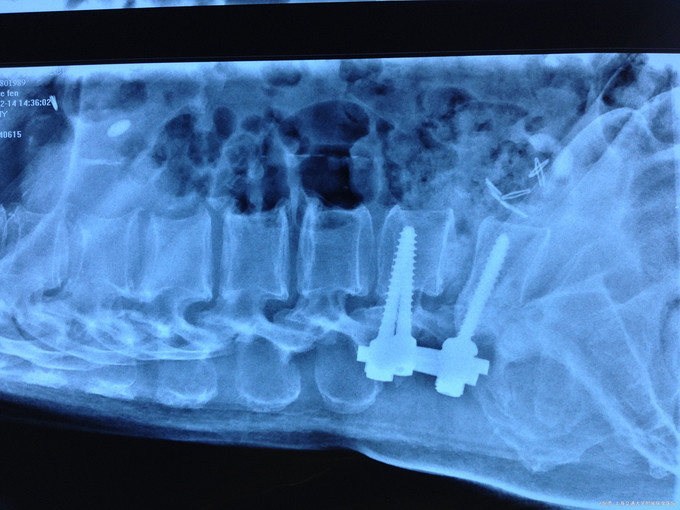

联合UBE手术治疗老年腰椎管狭窄症一例

750x526 - 83KB - JPEG